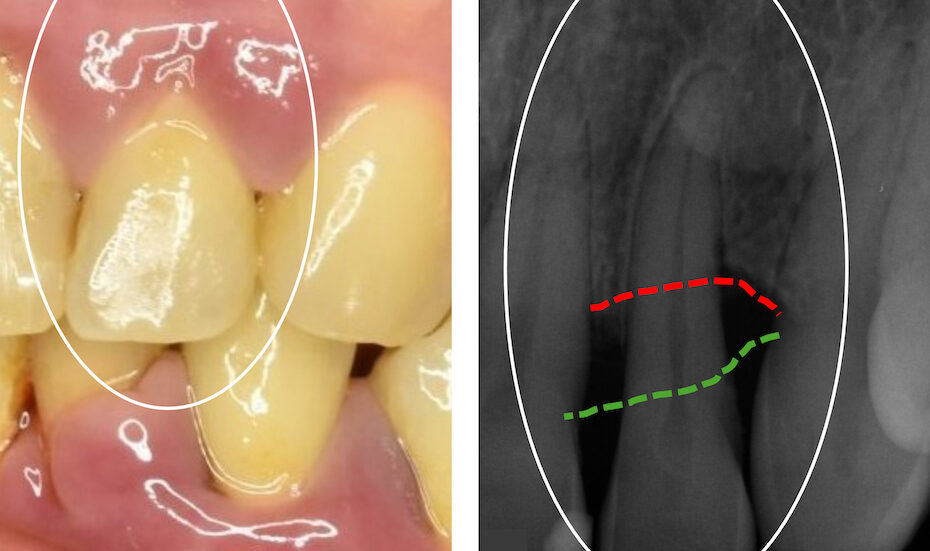

En amalgamfyllning . i tänderna består till hälften av kvicksilver. Ämnet är ett av de farligaste miljögifterna och kan orsaka allvarliga skador på hjärnan och det centrala nervsystemet. Sverige har sedan länge arbetat mot ett globalt förbud vilket nu har beslutats.